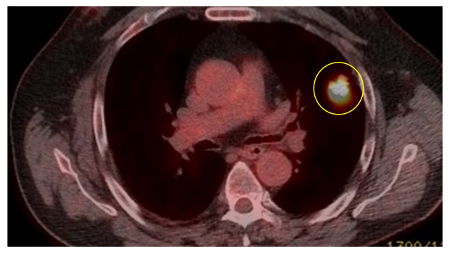

O modelo de Herder (que incorpora a avidez de fluordesoxiglucose F-18 [FDG]) foi considerado mais preciso em pacientes submetidos à avaliação de nódulos pulmonares por tomografia por emissão de pósitrons (PET-CT).[38][39] As diretrizes do Reino Unido recomendam que determinados pacientes (probabilidade pré-teste de neoplasia maligna >10% e componente sólido de um nódulo maior que o tamanho do limiar local [geralmente 8 a 10 mm]) sejam avaliados por PET-CT e que o modelo de Herder seja usado para determinar o risco posteriormente.[4][40]

18 F-FDG-PET/TC

Uma metanálise indicou uma sensibilidade de 96.8% e uma especificidade de 77.8%.[41] Isso se traduz em uma razão de probabilidade de 4.36 para neoplasia maligna, dado um teste positivo, e em uma razão de probabilidade de 0.04 para neoplasia maligna, dado um teste negativo. Resultados falso-positivos podem ocorrer em nódulos benignos metabolicamente ativos (por exemplo, infecções) e resultados falso-negativos podem ocorrer com tumores com atividade metabólica relativamente baixa, como carcinoma bronquíolo-alveolar ou tumores pequenos (5 a 8 mm).[42]

O exame PET-CT pode subestimar o risco de neoplasia maligna em relação aos nódulos puros com opacidade em vidro fosco, por causa da falta de tecido sólido suficiente para captar a FDG.

A PET pode ter função no estadiamento de tumores e tem um valor preditivo negativo especialmente elevado na exclusão do envolvimento mediastinal.[43][Figure caption and citation for the preceding image starts]: Cortes de tomografia computadorizada (TC) de dois casos com nódulos perifissurais benignos. Observe as margens lisas e a fissura adjacente normal e intactaDo acervo de Dr. George Tsaknis, MD, PhD, FRCP (Londres), MRQA, MAcadMEd, PGCert; usado com permissão [Citation ends].

[Figure caption and citation for the preceding image starts]: PET-CT com 18-fluordesoxiglucose (18-FDG) mostrando lesão periférica de alta captação no pulmão esquerdo. A ressecção cirúrgica confirmou câncer pulmonar de células escamosas moderadamente diferenciadoDo acervo de Dr. George Tsaknis, MD, PhD, FRCP (Londres), MRQA, MAcadMEd, PGCert; usado com permissão [Citation ends].